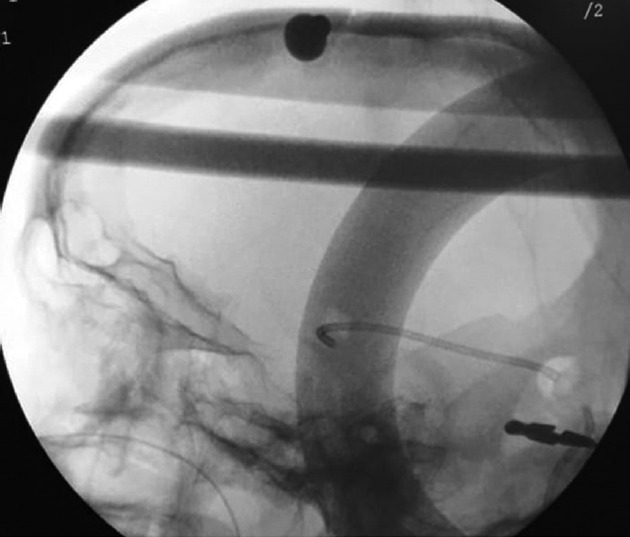

Background: Ventricular catheter (VC) misplacement is one of the most common causes of ventriculoperitoneal (VP) shunt malfunction and revision surgery. Most of the VC placements are done by freehand method. We evaluated the use of intraoperative fluoroscopy for assessing VC placement.

Materials and methods: A total of 70 patients were enrolled in the study. Patients with hydrocephalus who required cerebrospinal fluid diversion were enrolled in the study. Thirty-five patients were placed in the control group (patients in whom intraoperative fluoroscopy was not done), and 35 patients were placed in the test group (patients in whom intraoperative fluoroscopy was done). Patients with trapped ventricles and multiloculated hydrocephalus were excluded from the study. VP shunt insertion was done through standard Keen's point.

Results: The positioning of VC was optimal in 40 patients, with a significant difference between the test group and the control group. Gross malpositioning was seen in seven patients: four in the test group and three in the control group. All gross malpositioned VCs in the test group were corrected intraoperatively. VC crossing midline was less in the test group as compared to the control group.

Conclusion: Fluoroscopy is an easy and cheap method to assess VC position intraoperatively. It is readily available and helps us in avoiding resurgery due to VC misplacement and subsequent blockage.